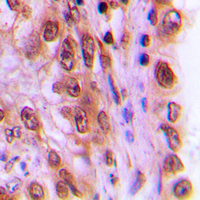

IHC (Immunohiostchemistry)

(Immunohistochemical analysis of c-Rel (pS503) staining in human lung cancer formalin fixed paraffin embedded tissue section. The section was pre-treated using heat mediated antigen retrieval with sodium citrate buffer (pH 6.0). The section was then incubated with the antibody at room temperature and detected using an HRP conjugated compact polymer system. DAB was used as the chromogen. The section was then counterstained with haematoxylin and mounted with DPX.)